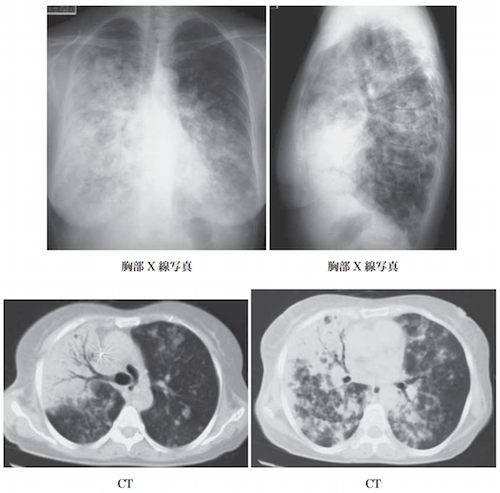

進行すると拘束性肺疾患を発症し肺拡散能が低下する。臨床的には、患者は咳嗽や呼吸困難を示す。また、胸痛や関節痛、体重減少や発熱などの症状が現れる。まれに肝臓など他の臓器に肉芽腫を生じることがある。